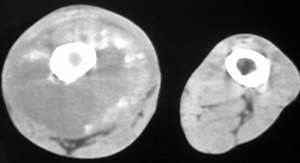

标题: CT4055:骨肉瘤?

男56涨疼5-6月

右股骨下端包绕股骨见巨大软组织肿块,密度部俊,周围见瘤骨,下端骨皮质侵蚀变薄,骨质周围无骨膜反应, 考虑右股骨软骨肉瘤。

右股骨下段周围软组织肿块伴钙化,相邻股骨骨皮质受累,考虑软组织来源恶性病变

右股骨下段骨肉瘤,软组织内瘤骨,软组织肿块。